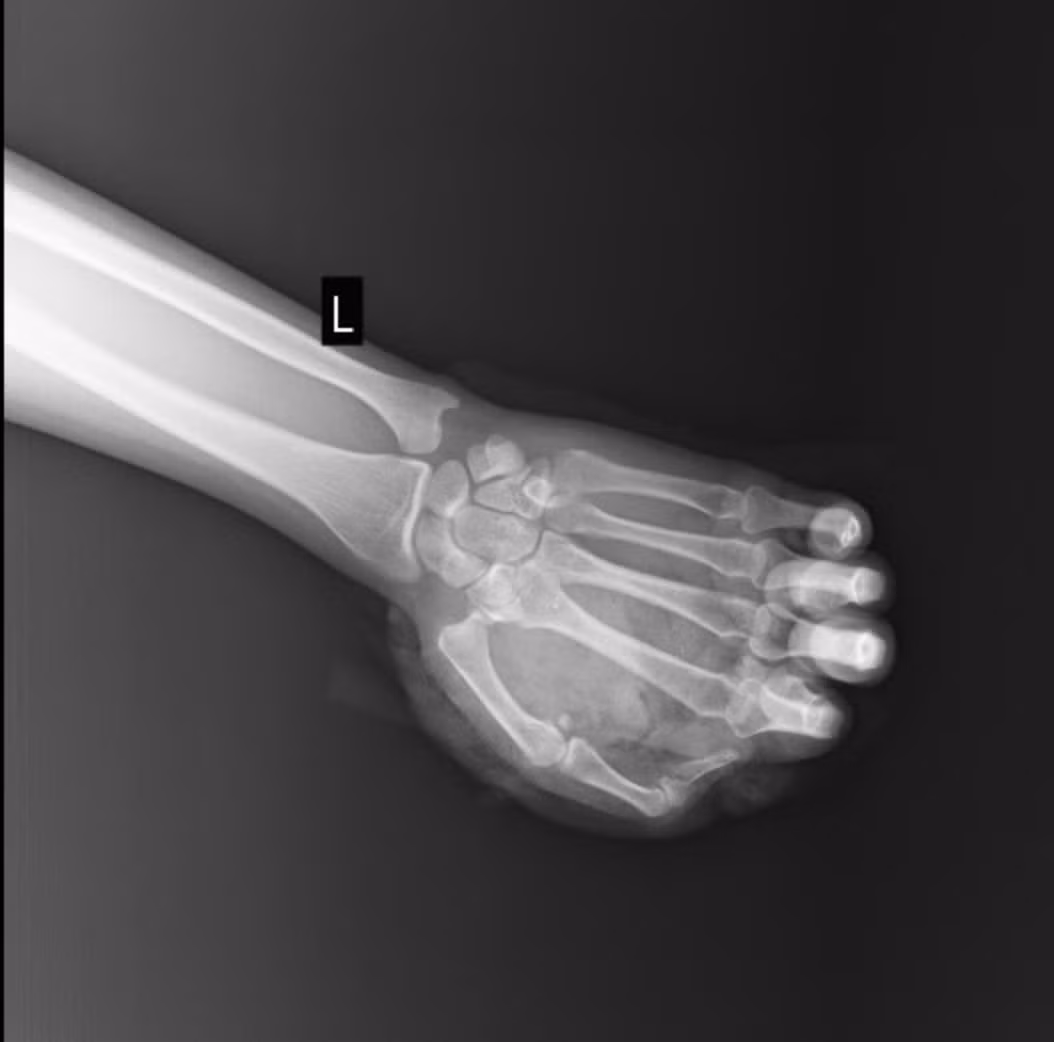

Người bệnh là nam giới trẻ tuổi, nhập viện trong tình trạng vết thương phức tạp bàn tay trái sau khi sử dụng pháo nổ. Theo lời kể của bệnh nhân, trong lúc đốt pháo, quả pháo bất ngờ phát nổ ngay trên tay, khiến bàn tay bị tổn thương nặng.

Ngay sau tai nạn, người bệnh được đưa đến cấp cứu tại Bệnh viện E. Khi thăm khám, bác sĩ ghi nhận người bệnh bị vết thương dập nát phức tạp bàn tay trái, chảy máu nhiều, nguy cơ tổn thương gân, mạch máu và thần kinh, có nhiều dị vật và mô hoại tử trong vết thương, nguy cơ mất chức năng bàn tay nếu không xử trí kịp thời…

Các bác sĩ nhận định, đây là tổn thương thường gặp trong tai nạn pháo nổ, có mức độ rất nghiêm trọng do lực nổ mạnh gây phá hủy tổ chức sâu như xương, gân, cơ, khớp… Vì vậy, các bác sĩ đã tiến hành xử trí khẩn cấp để bảo tồn tối đa chức năng bàn tay cho người bệnh.

Tổn thương trên phim chụp - Ảnh BVCC